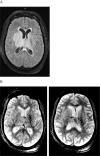

Background and purpose: Coronavirus disease 2019 (COVID-19) is a global pandemic that causes flu-like symptoms. There is a growing body of evidence suggesting that both the central and peripheral nervous systems can be affected by SARS-CoV-2, including stroke. We present three cases of arterial ischemic strokes and one venous infarction from a cerebral venous sinus thrombosis in the setting of COVID-19 infection who otherwise had low risk factors for stroke.

Results: There were 3 cases of arterial ischemic strokes and 1 case of venous stroke: 3 males and 1 female. The mean age was 55 (48-70) years. All arterial strokes presented with large vessel occlusions and had mechanical thrombectomy performed. Two cases presented with stroke despite being on full anticoagulation.